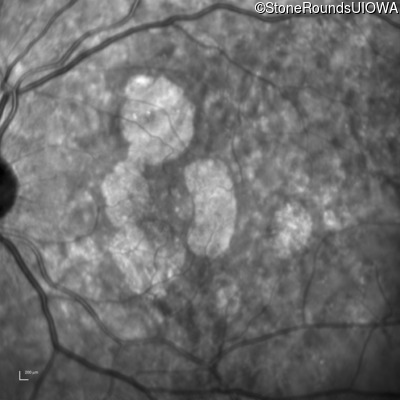

Infrared Fundus Photograph - Right - 20/20

Exemplar

Infrared Fundus Photograph - Left - 20/20 -1